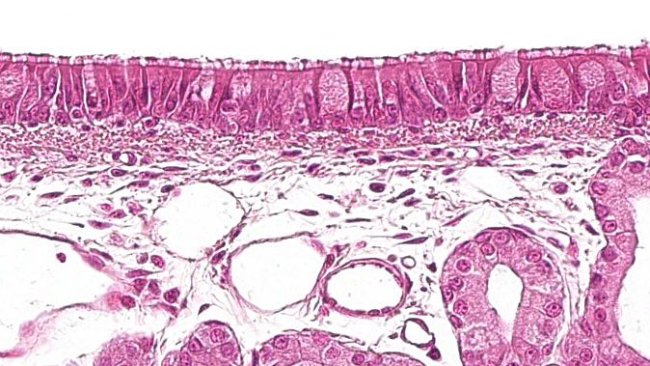

W artykule opisano główne zmiany charakteryzujące najważniejsze bakteryjne zapalenia płuc. Chociaż większość z nich to mikroorganizmy oportunistyczne, istnieją także czynniki bakteryjne, które same z siebie mogą powodować zmiany.

Jakie komórki składają się na obronę układu oddechowego świń? Jak się organizują i komunikują ze sobą?